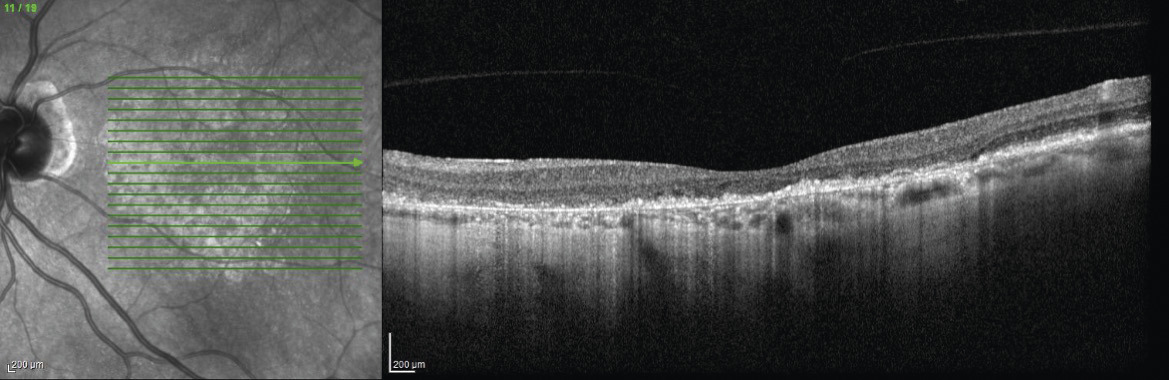

Le diagnostic est fait au fond d’œil et sur l’OCT où des dépôts lipidiques – appelés drusen – (fig. 8) sont observés. Ils peuvent être associés à des altérations de l’épithélium pigmentaire.

Cette forme entraîne une baisse d’acuité visuelle progressive ainsi que des scotomes centraux (fig. 9).

Le diagnostic est fait au fond d’œil et confirmé à l’OCT où l’on constate une atrophie des couches externes de la rétine correspondant aux photorécepteurs ainsi qu’une atrophie de l’épithélium pigmentaire.

Le diagnostic est le plus souvent posé par l’OCT, avec la présence d’un néovaisseau choroïdien sous rétinien et une activité exsudative avec décollement séreux rétinien. La présence du néovaisseau est initialement confirmée par l’angiographie (fluorescéine ou indocyanine) et l'OCT-angiographie selon le type de néovaisseau (fig. 10A).

L’œdème maculaire est une cause fréquente de baisse d’acuité visuelle progressive (fig. 10B).

Le diagnostic est fait grâce à l’OCT, qui montre un épaississement maculaire avec des logettes intrarétiniennes ou du liquide sous-rétinien. Lorsqu’il est important, une image en « pétales de fleur » peut être visible au fond d’œil.

Membrane épimaculaire et trou maculaire

Ce sont des pathologies de l’interface vitréorétinienne (fig. 11). Les signes fonctionnels constituent le syndrome maculaire : métamorphopsies, baisse d’acuité visuelle et/ou scotome central. Le diagnostic est fait à l’examen du fond d’œil (« reflet cellophane » pour la membrane) et confirmé par l’examen en OCT. La prise en charge thérapeutique est chirurgicale.